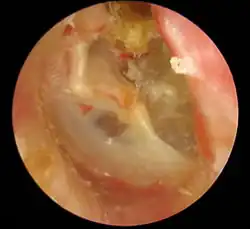

Sinus-tympanicus-Cholesteatom, linkes Ohr

Das sekundäre Cholesteatom entsteht auf Basis einer entzündlich entstandenen, tief eingezogenen, hauchdünnen (= atrophischen) Trommelfellnarbe im hinteren Trommelfellanteil (Sinus-tympanicus-Cholesteatom) oder durch eine sogenannte Mittelohr-Atelektase, bei der das gesamte Trommelfell atrophisch verändert und an die innere Wand des Mittelohres angesaugt ist (Pars-tensa-Cholesteatom). Durch entzündliche Veränderungen und Ansammlung von weißlichem Cholesteatommaterial imponieren die Retraktionstaschen oft als Trommelfellperforationen. Echte randständige Perforationen nach nekrotisierender Otitis (z. B. bei Scharlach) als Ausgangspunkt eines Cholesteatoms sind heute eher selten.

Die Diagnose wird mit Hilfe der Ohrmikroskopie gestellt. Der typische Befund ist ein Defekt in der Pars tensa oder Pars flaccida des Trommelfells mit Nachweis weißlich-gelber Schuppen oder Zellmassen in der Läsion. Nicht selten finden sich Polypen aus Granulationsgewebe. Untersucht man das Trommelfell durch die direkte Otoskopie, sieht man häufig eine Perforation des Trommelfells am oberen oder hinteren Rand.